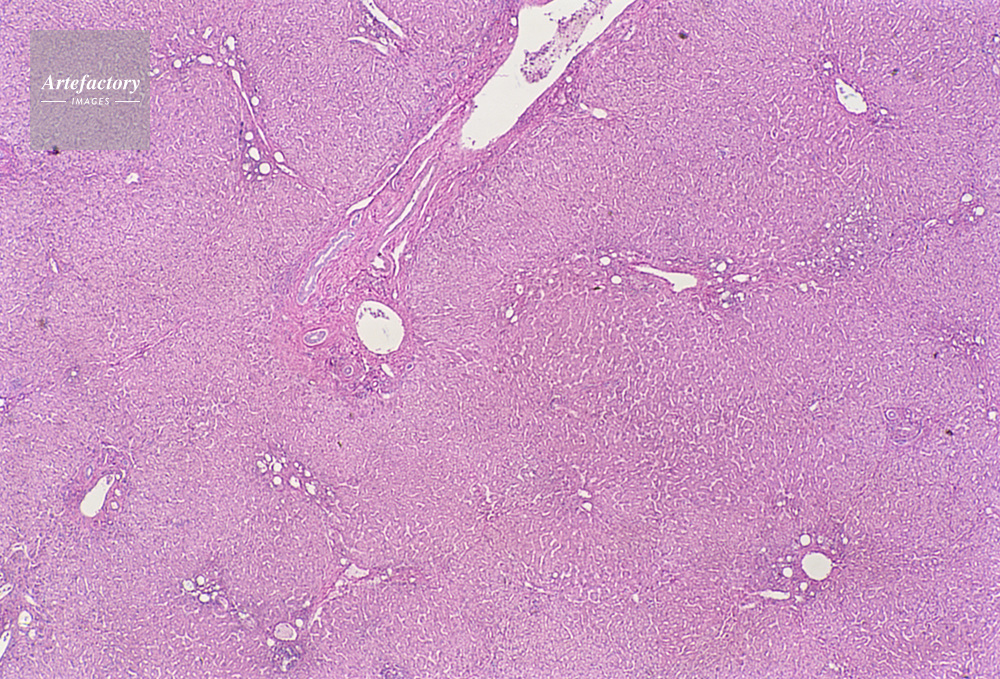

| 作品タイトル | 顕微鏡写真 | モデルリリース | なし | |

| キャプション | 人,ヒト,人物,肝臓 | 制限事項 | ||